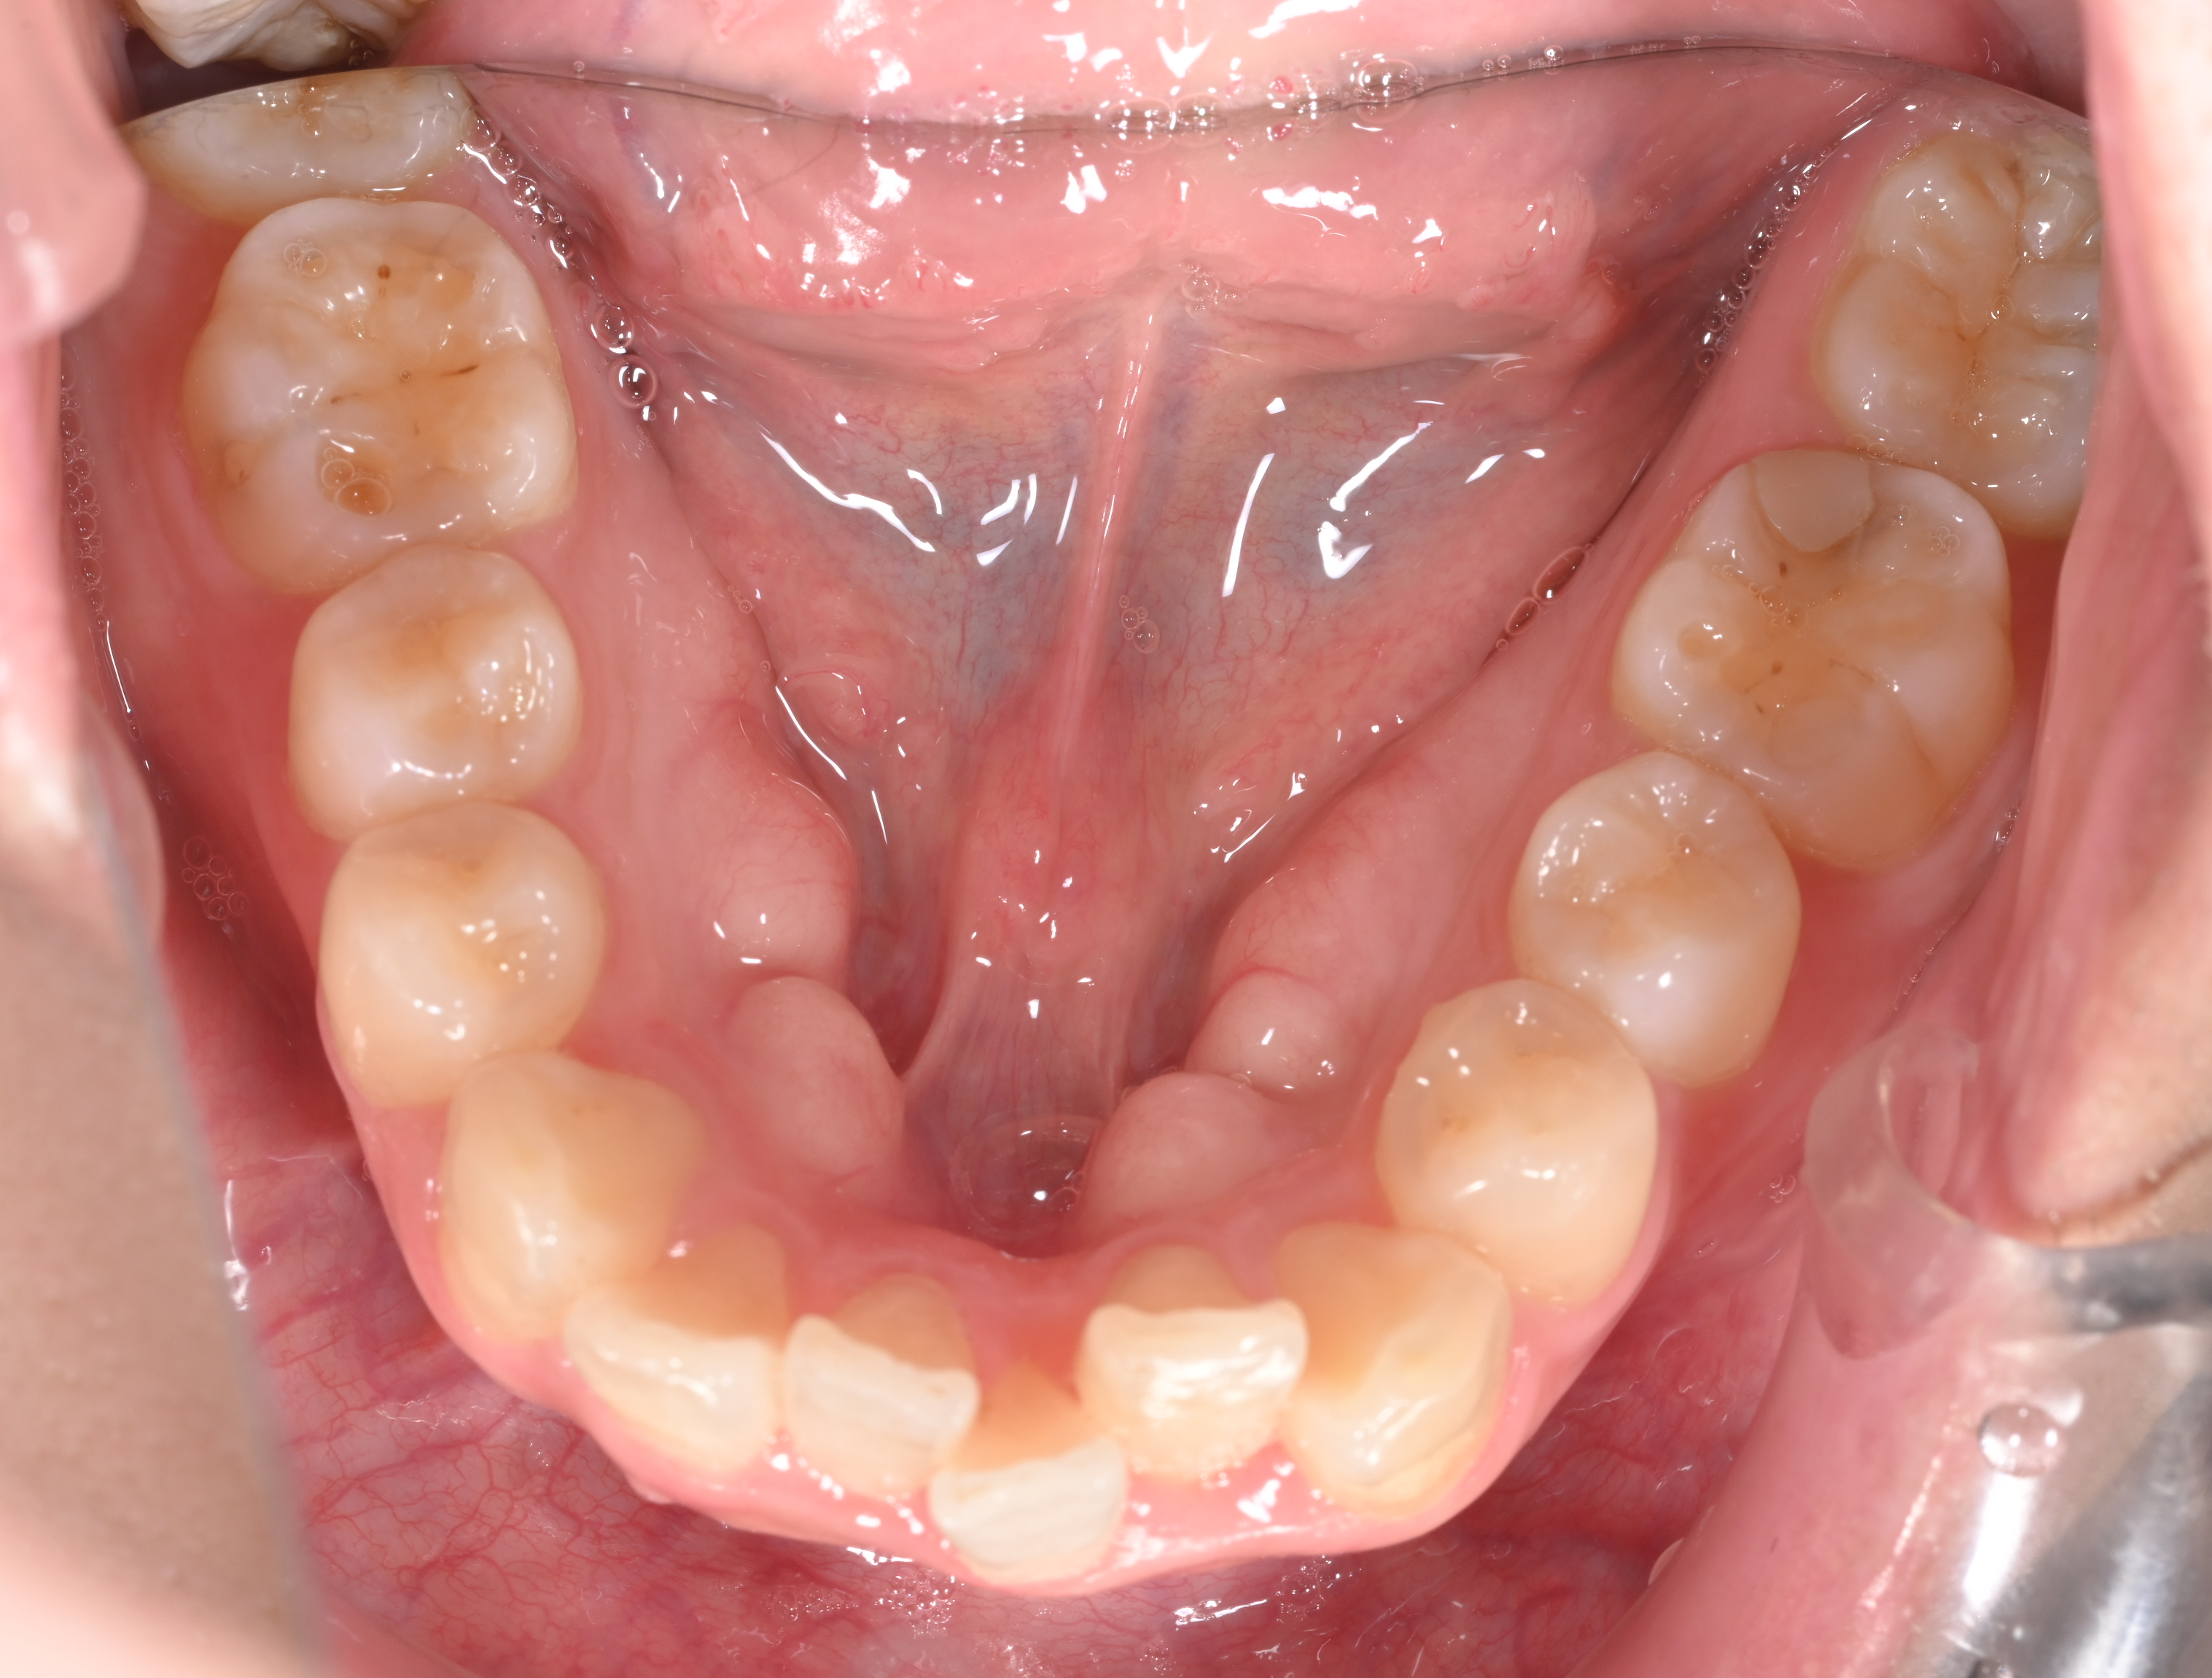

| 主訴 | 前歯のがたつきと出っ歯が気になる |

初診時の画像

確かにお顔を拝見すると、上の歯も下の歯もやや出ている感じがしますね。このような場合の治療法としては基本的には真ん中の歯の抜歯を行い、そのスペースを使用して、前歯をひっこめるのが定石です。もしくは少しずつ奥歯を後ろに移動し、さらに少し歯を削ることでスペースを作り前歯を後ろに引くのも一つです。大きく前歯をひっこめる場合にはやはり抜歯が妥当です。もう一つのご質問のマウスピース矯正で治療が可能かという質問ですが、それは可能です。しかし抜歯を行う場合には、マウスピース矯正だけでなくワイヤー矯正も併用する可能性があります。

下の前歯の叢生(がたつき)と出っ歯が気になるを主訴に来院された方の矯正相談についてのお話でした。マウスピース矯正で抜歯は難しいと言われた方もいると思いますが、近年ではマウスピース矯正も進化してきており一概に抜歯が対象外というわけではなくなってきています。実際に適応なのかどうかは矯正を行う歯科医に一度相談してみることをお勧めいたします。